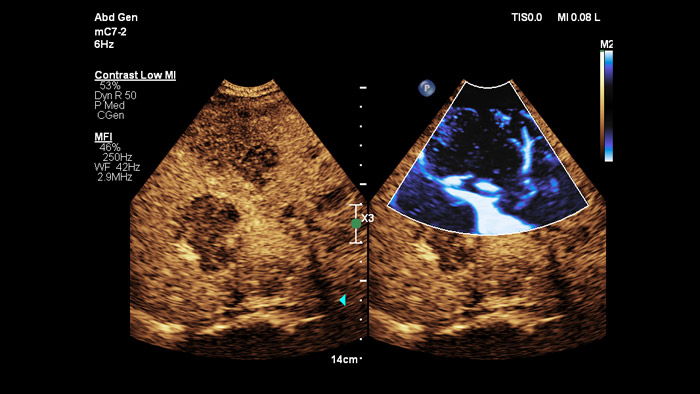

ElastQ fornisce una valutazione in tempo reale 2D della rigidità dei tessuti con la tecnologia 2D shear-wave (2D-SWE) non invasiva, riproducibile e facile da eseguire. ElastQ offre inoltre la possibilità di effettuare misurazioni retrospettive sulle immagini memorizzate e include una mappa di confidenza per una visualizzazione adeguata della propagazione delle onde trasverse.

ElastQ Imaging